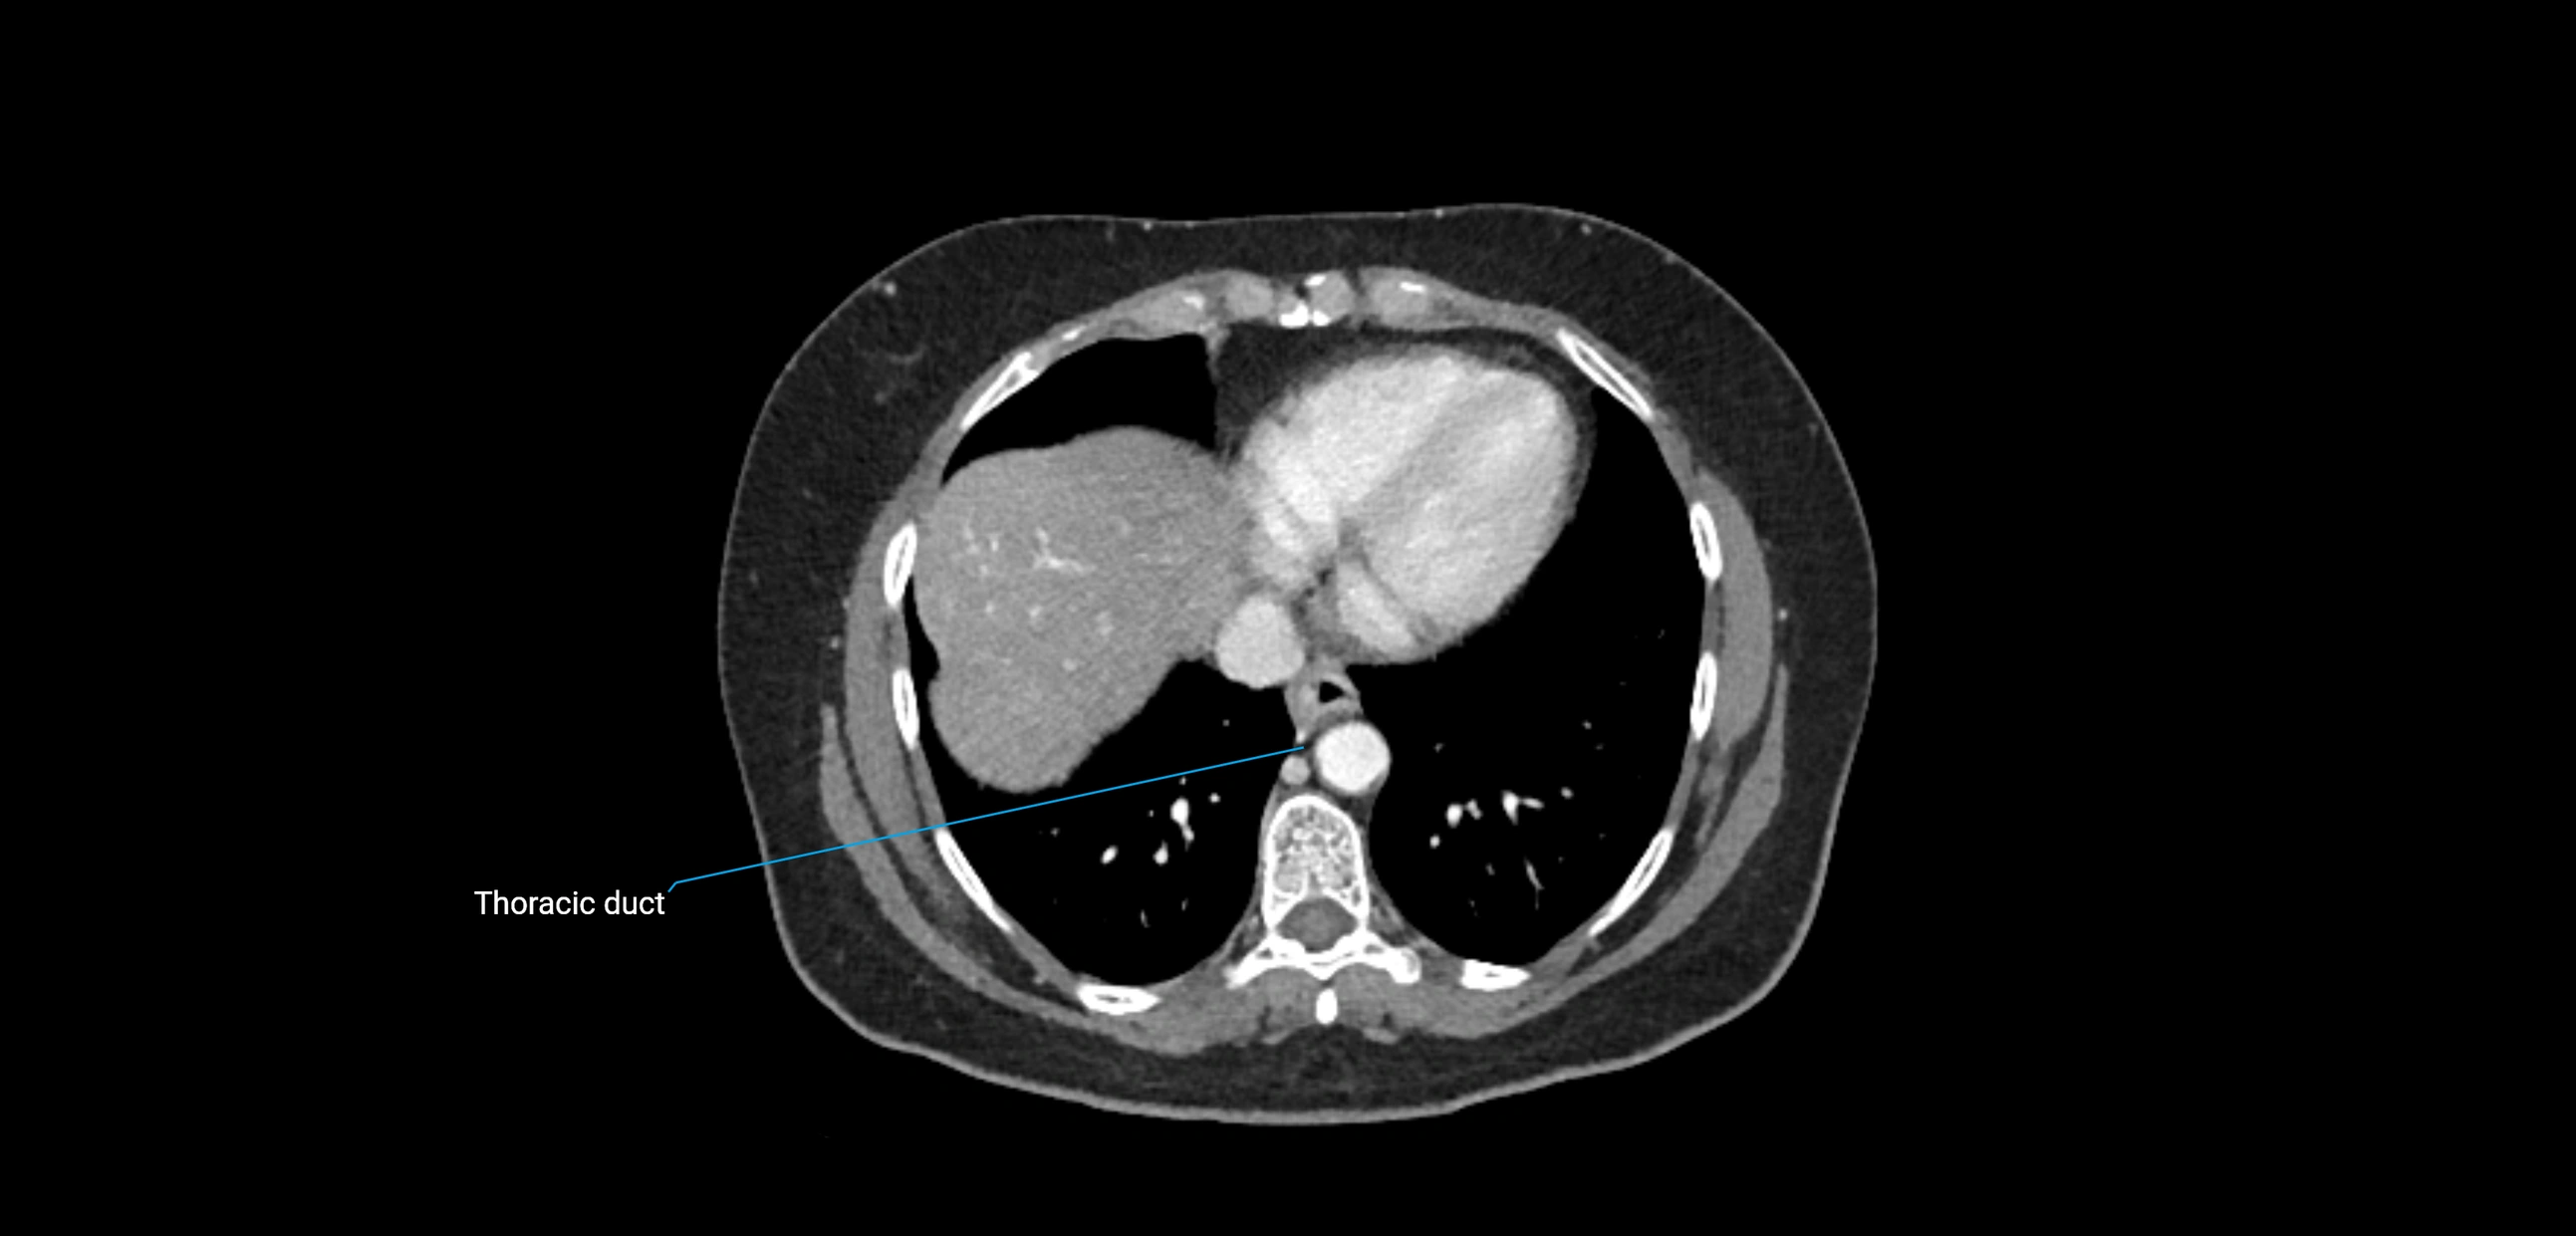

MRI images

image